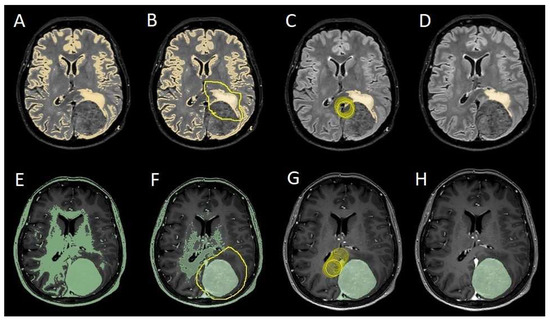

The process begins with an automatic thresholding technique to identify initial regions of interest based on intensity values (Figure 2A,E). This is followed by manual refinement to enhance accuracy and delineate precise boundaries (Figure 2B,C,F,G). The final segmentation provides volumetric measurements for both the tumor and the PE, aiding in quantitative analysis (Figure 3). The included patients’ pre- and post-treatment clinical data were retrospectively extracted from our center’s computerized database. Collected data included demographic information, preoperative clinical details (presence or absence of epilepsy, onset symptoms, ASM therapy and number of ASMs taken, and radiological characteristics of the meningioma), and postoperative data (Engel class [16], persistence or discontinuation of ASMs, ASM discontinuation timing, and possible postoperative functional deficits). A single examiner conducted data collection to minimize subjective variability in assessments. Surgical procedures were performed using a transcranial approach under general anesthesia. We excluded cases of surgical resection performed via an endoscopic endonasal approach. Cases of postoperative death (within one year after surgery) were excluded. The extent of resection (EOR) was determined based on the postoperative MRI (usually one month after surgery) and classified according to the Simpson grading system [17]. This study included cases of complete macroscopic meningioma resection (Simpson I, II, and III). Cases with residual tumor persistence or recurrence after surgery (Simpson IV and V) were excluded (Figure 4).

To evaluate which independent variables (meningioma volume, PE volume, the ratio between meningioma and PE volume, and the presence of preoperative epilepsy) influenced the dependent variable (seizure outcome), we performed a binomial logistic regression, which required converting continuous variables into binary values. For PE volume, values < 1 cm3 were coded as 0 (Figure 4), and values ≥ 1 cm3 as 1 (Figure 5). The cut-off was set at 3 cm3 for tumor volume, and for the volume ratio, the cut-off was 1. The absence of preoperative epilepsy was coded as 0, while its presence was coded as 1. Regarding seizure outcome, Engel IA cases were coded as 0, and cases classified as Engel > IA were coded as 1.

Figure 4. Segmentation process for PE < 1 cm3. (A,E) Automatic thresholding technique to identify initial regions of interest based on intensity values, respectively, for the PE and the meningioma. (B,F) Partially automatic erase of redundant signal with “erase outside” tool. (C) Precisely definition of boundaries of edema through manual erasure, cutting all around redundant signal. (G) Manual erasing boundaries for tumor volume. (D,H) Final segmented volumes. PE: peritumoral edema.